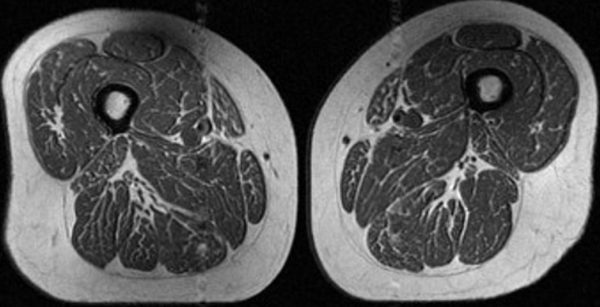

На снимке изображен кусок мяса с ярко выраженной мраморностью, напоминающий высококачественный стейк с обильными мелкозернистыми прожилками жира. Но это не ужин. Это МРТ бедра 62-летней женщины, которая получает 87% своих годовых калорий из ультрапереработанных продуктов.

Скрытые жировые прослойки, прячущиеся между мышечными волокнами и внутри них, могут сигнализировать о серьезных проблемах со здоровьем, заявил Аккая, ведущий автор нового исследования, в котором анализировалось влияние ультрапереработанных продуктов на внутримышечный жир у людей, подверженных риску развития остеопороза коленного сустава.

У 61-летней женщины, участвовавшей в исследовании, также наблюдалась жировая мраморность в мышцах бедра, но она была не такой интенсивной. Около 29% ее годового рациона составляли ультрапереработанные продукты.